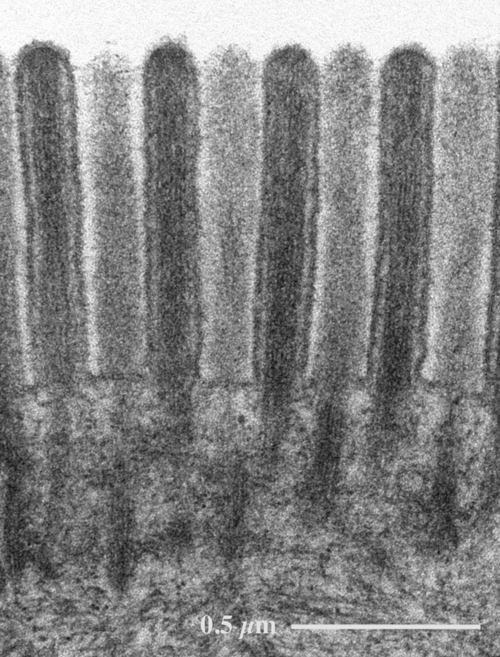

TEM)とは、電子顕微鏡の一種である。 観察対象に電子線をあて、透過してきた電子線の強弱から観察対象内の電子透過率の空間分布を観察するタイプの電子顕微鏡のこと。 また、電子の波動性を利用し、試料内での. 4 問題解説 技術-1第52回細胞検査士認定試験 一次筆記試験 5 まとめ:問題 技術-1第52回細胞検査士認定試験 一次試験筆記. 薄さ70 - 80 nm 超薄切片の透過型電子顕微鏡画像 Transmission electron microscopic image of 70 - 80 nm ultra thin section 糸球体の電子顕微鏡像 円形の毛細血管を足細胞が取り囲む構造が観察されます。 糸球体の拡大像.

透過型電顕試料作製の実際 -透過型電子顕微鏡を用いたアポトーシス細胞の観察-* 日下部 健 I. こと,感覚細胞に2種類(I型 ・II型毛細胞)が 存在 することは電顕以前にわかっていたが,こ のほか求心 神経終末と遠心神経終末の特徴や毛細胞との関連など 電子顕微鏡によって全貌が明らかにされてきた.ま た 耳石や耳石膜5)49)71),感覚毛やrootlet, basalbody,. 3 – 走査電子顕微鏡 (SEM)」で走査型についてはこのEkuipp Magazineですでにご紹介済みですので、今回は透過型電子顕微鏡(Transmission Electron Microscope, 以下TEM)についてです。.